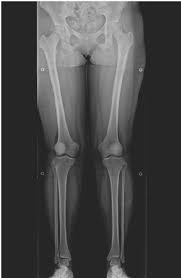

2.1 정상 정렬과 비정상 정렬

정상적인 다리 정렬에서는 체중이 무릎 중앙에 균등하게 분포되며, 관절에 가해지는 압력이 일정하다. 하지만 비정상적인 정렬, 즉 O자형(내반슬)이나 X자형(외반슬) 다리는 무릎 관절의 특정 부위에 과도한 압력을 가하게 된다. 이러한 압력 불균형이 장기간 지속되면 관절 연골이 점진적으로 마모되면서 관절염이 발생할 가능성이 높아진다.